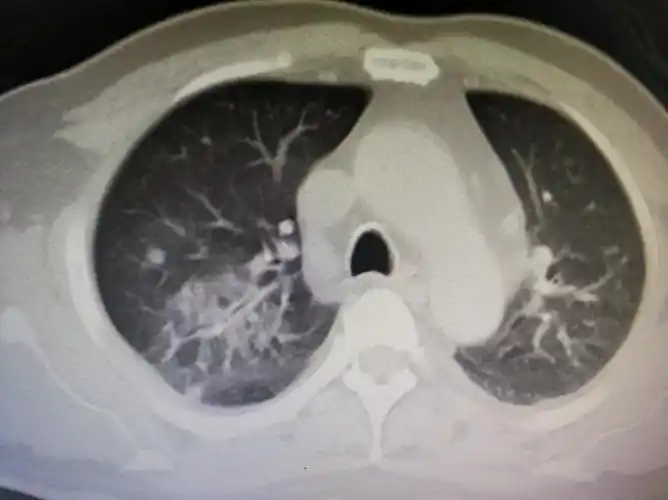

胸部ct双肺继发性肺结核,右上肺空洞形成.

耐药肺结核治疗第14个月!

请高手看看肺结核ct

肺结核如何诊断从胸部ct到实验室检查一文讲清世界防治结核病日

总在肺结核影像上「翻车」?老司机带带你